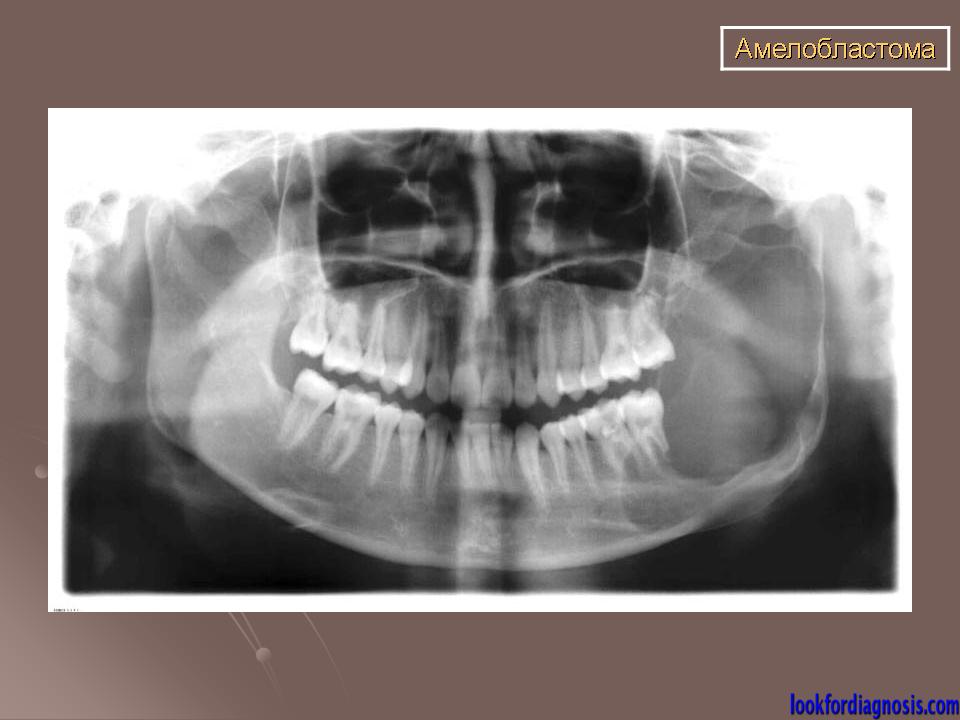

Амелобластома

ID: 13276 Ameloblastoma Dr Morlie L Wang - 21 Mar 2011 Pathologically proven ameloblastoma.

Ортопантограмма пациента